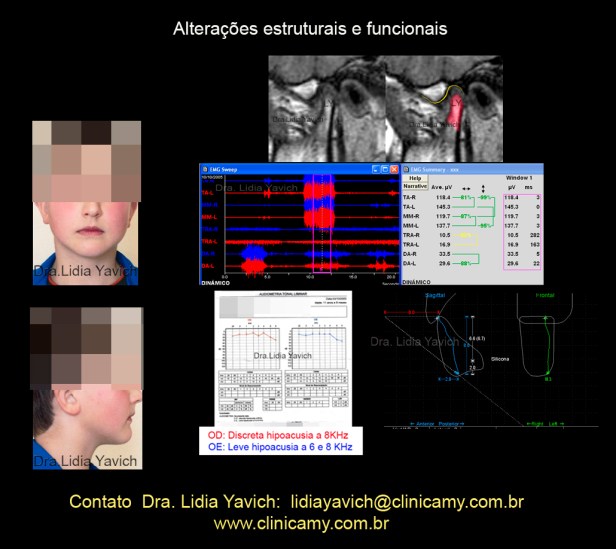

RNM TI: Um corte sagital da ATM esquerda e da ATM direita em boca fechada.

Podemos observar facetas anteriores nas cabeças mandibulares tanto do lado direito como esquerdo. Na ATM direita o disco está levemente luxado anteriormente. Na ATM esquerda a luxação é mais evidente, estando a cabeça da mandíbula apoiada nos ligamentos retro discais.

RNM TI: Um corte sagital da ATM esquerda e da ATM direita em boca aberta.

Podemos observar facetas anteriores nas cabeças mandibulares tanto do lado direito como esquerdo. Ambos os côndilos mandibulares não conseguem transladar estando diminuída a abertura bucal.

Registro cinesiógrafico inicial: perda da velocidade quando o paciente abre e fecha a boca. Não há coincidência entre as trajetórias de abertura e fechamento na vista sagital do registro. Limitação na abertura bucal, o paciente consegue abrir só 32,9 mm.

Eletromiografia de superfície dinâmica do paciente em oclusão habitual antes do tratamento.

São medidos:

Temporais anteriores direito e esquerdo.

Masseteres direito e esquerdo

Digástricos direito e esquerdo

Trapézio superior direito e esquerdo

Ativação dos digástricos no fechamento, sendo que estes músculos só devem ser ativados na abertura.

Importante ativação dos trapézios superiores mesmo o paciente sendo instruído a abaixar os ombros ele ativa ambos os trapézios durante todo o exame.

A primeira audiometria do paciente revela uma discreta hipoacusia no ouvido esquerdo e uma leve hipoacusia no ouvido direito.

Lesões estruturais podem produzir alterações funcionais que por sua vez aumentam as alterações estruturais.

Alterações estruturais e funcionais.